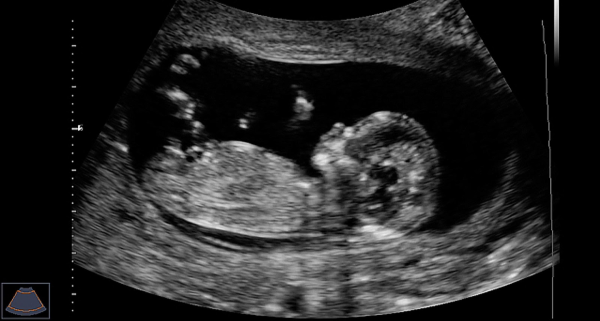

Наверное, самый узнаваемый визуальный образ УЗИ — это еще не рожденный человек в утробе матери. И не зря этот образ связан с беременностью.

Еще не родившийся, но уже человек

Основной принцип такого исследования — излучать в мягкие ткани организма ультразвуковой сигнал и ловить его отражения. Эти отражения визуализируют в виде картинки.

УЗИ идеально подходит именно для мягких тканей. Живот, сердце, сосуды. А еще этот метод исследования безопасен и не награждает пациента дозой облучения.

Потому его смело назначают всем, вплоть до беременных женщин и еще не родившихся детей.